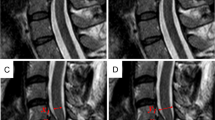

All subjects underwent a MRI scan (3T, MAGNETOM SkyraFit, Siemens Healthcare, Erlangen) including sagittal and axial standard clinical T2w sequences and axial 2D phase contrast imaging encoding cranio-caudal spinal cord motion in each cervical segment (Fig. 1a). Slice orientation in phase contrast imaging was adjusted perpendicular to the spinal cord. The phase contrast sequence was cardiac gated through peripheral pulse triggering using a finger clip. The venc (velocity encoding) value of the phase contrast sequence was set to 2 cm/s based on previous findings of cord motion4,5,6,7,18. During one cardiac cycle velocity signal was assessed within 20 time points and 128 measurements were averaged per segment. Total scanning time of the whole protocol was 23 min.

Steps in spinal cord motion evaluation. Spinal cord cranio-caudal motion was measured by axial MRI phase contrast imaging in each cervical segment (a; sagittal T2 image; red lines identifying the cervical segments; arrow illustrating motion). Motion was encoded into grey values of the MRI image within 20 timepoints of one heartcycyle. Velocity values were calculated by the mean of collected grey value within the predefined region of interest (b; axial phase contrast image; red circle illustrating predefined ROI) and the used velocity encoding in the sequence (2 cm/s). Due to a technically caused offset error (c; uncorrected motion signal during one heartcycle (0–100%); arrow indicating offset error) raw velocity values were misleading overestimated. Subtracting the mean of all 20 velocity values from each single value could sufficiently correct for the offset error (d; corrected motion signal during one heartcycle (0–100%)). Readouts of spinal cord motion used were amplitude of the motion signal, ranging from the maximum negative to the maximum positive value, maximum cranial velocity, maximum caudal velocity and the displacement (=area under curve of velocity signal).

As phase contrast imaging is a relative measure of motion a so-called “phase drift”10 leads to an offset error of the raw data ending in misleading velocity values (Fig. 1c). Therefore, phase drift conducts to an over- or underestimation in the velocity measurements and a correction for phase drift is needed. In our analysis phase drift correction was done by subtraction of the mean of all 20 velocity measurements within one cardiac cycle from the raw velocity value at each time point (Fig. 1d), as net motion of the spinal cord over one cardiac cycle is assumed to be 0 (start and end location of the spinal cord is expected to be at the same position - assuming mean velocity has to be 0).